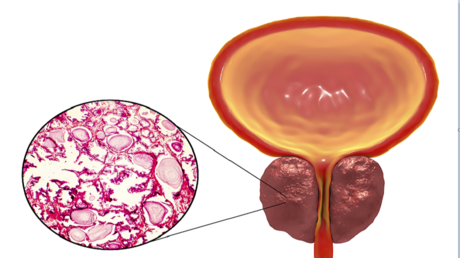

نهج مبتكر لإبطاء سرطان البروستات وتقويض انتشاره

ذكرت مجلة أن فريقا من العلماء في كلية لندن الجامعية تمكن من اكتشاف تركيبة دوائية قادرة على إبطاء تطور سرطان البروستات، أحد أخطر أنواع السرطانات لدى الرجال.

وأشارت المجلة إلى أن العلماء، في إطار المرحلة الثالثة من دراسة، اكتشفوا أن إضافة دواء “نيراباريب” إلى العلاج المعتمد، الذي يشمل إبيراتيرون وبريدنيزولون، يمكنه إبطاء تطور سرطان البروستات العدواني في الجسم.

وشارك في الدراسة نحو 700 شخص يعانون من سرطان البروستات النقيلي، لديهم طفرات في جينات إصلاح الحمض النووي مثل 1 و2 و2 و2. وتُعد هذه الطفرات سببا في عدوانية الورم وتقليل فعالية العلاجات التقليدية.

ولاحظ الباحثون أن إضافة نيراباريب إلى الأدوية المعتمدة خفض خطر تطور الورم بنسبة 37٪، أما المرضى الذين لديهم طفرات 1 و2، فقد ساعد الدواء في خفض خطر تطور الورم إلى النصف تقريبا. كما تبين أن أعراض المرض تتفاقم ببطء مضاعف تقريبا لدى المرضى الذين تلقوا “نيراباريب” مقارنة بمن حصلوا على العلاجات التقليدية.

تأثير تقلبات الطقس على صحة البروستاتا

وأشار البروفيسور جيرهارد أتارد، رئيس فريق البحث، إلى أن النتائج تؤكد أهمية الاختبارات الجينية عند تشخيص هذا النوع من الأورام، حيث تتيح اختيار علاج دقيق يطيل حياة المرضى بشكل ملحوظ، خصوصا لأولئك الذين لا تجدي معهم العلاجات التقليدية نفعًا.

ويعتقد العلماء أن هذا الاكتشاف سيمهد الطريق لتطوير نهج جديد لعلاج سرطان البروستات، لا سيما لدى الأشخاص الذين لديهم طفرات في جينات إصلاح الحمض النووي.